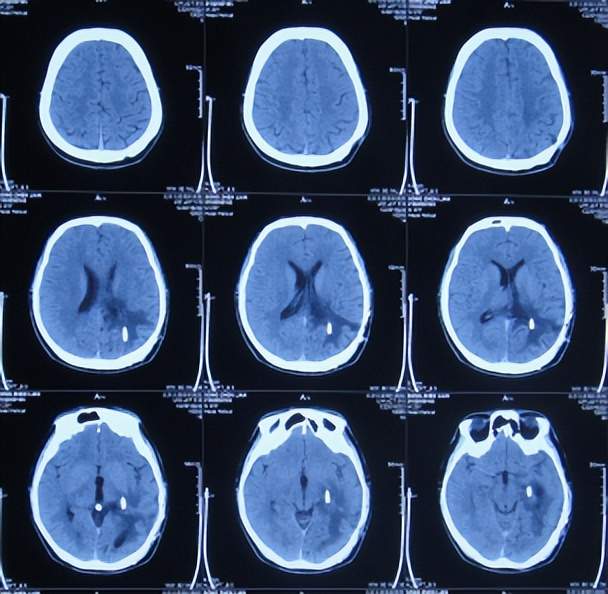

入院后5天即2021年1月18日,查头颅CT增强示颅内占位(图-4)。

图-4:2021年1月18日头颅CT增强

图-5:2021年1月20日头颅CT

颅内占位切除术后次日即2021年1月21日,查头颅CT示脑瘤术后改变(图-6)。

图-6:2021年1月21日头颅CT

颅内占位切除术后第2天即2021年1月22日,头痛基本消失,脑瘤病理回报脑膜瘤;查头颅CT示脑室周水肿(图-7)。

图-7:2021年1月22日头颅CT

脑膜瘤术后第5天即2021年1月25日,查头颅是示水肿减轻(图-8)。

图-8:2021年1月25日头颅CT

术后第7天即2021年1月27日,拔除脑室外引流管(图-9),改行腰大池引流并给予抗感染治疗。

图-9:2021年1月27日头颅CT